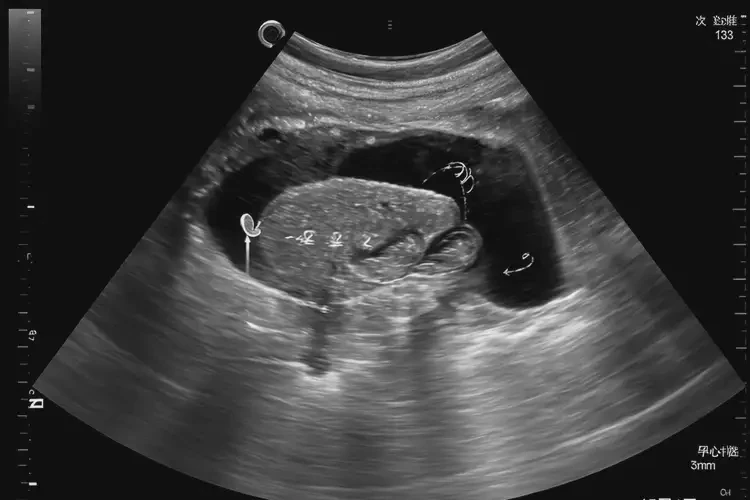

孕5周4天胎心133正常吗

133次/分钟

在孕5周4天时,胎心133次/分钟属于正常范围。胎心率是指胎儿心脏每分钟跳动的次数,正常情况下,胎心率在120-160次/分钟之间波动。以下是关于胎心率的详细解释:

孕5周4天胎心133正常吗(图1)